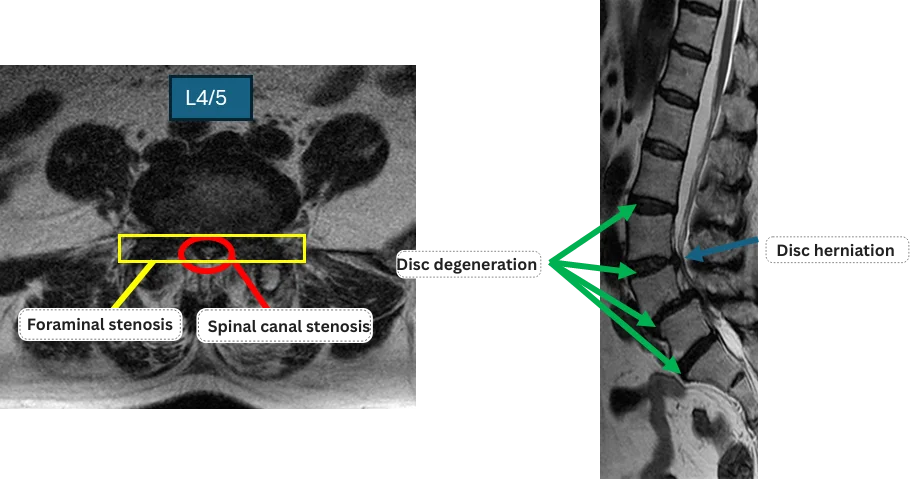

L1/2: Nothing unusual

L2/3: Disc degeneration

L3/4: Disc degeneration, disc herniation

L4/5: Disc degeneration, spondylolisthesis, spinal canal stenosis, foraminal stenosis

L5/S: Disc degeneration

The above findings were also observed on the imaging.

The disc degeneration and spinal stenosis at L2/3, L3/4, L4/5, and L5/S are highly likely to be the primary causes of her symptoms.